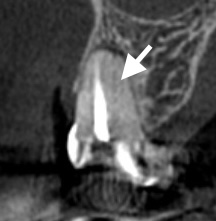

CTを撮影すると、

未処置と思われる根管の存在が疑われました。

MB2(近心頬側第2根管)

は、非常に見つけにくい位置にあります。

肉眼では確認が難しく、

過去の治療で処置されていないこともあります。